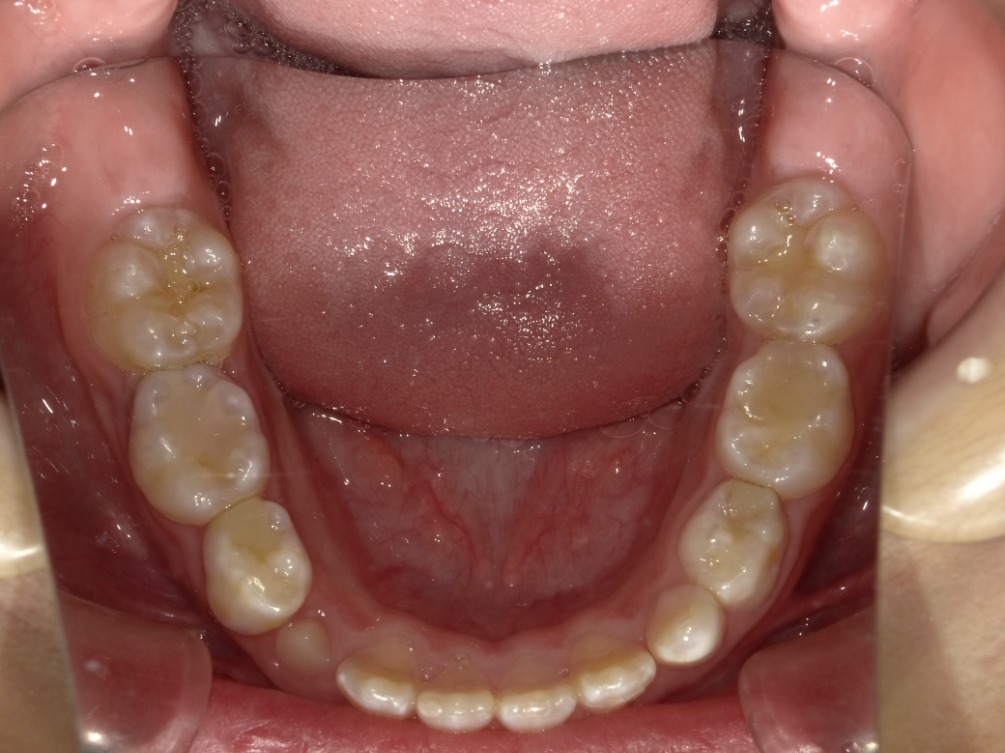

下顎

| 治療内容 | インビザライン・ファースト |

|---|---|

| 治療詳細 | 反対咬合や叢生、開咬を整えるために、歯の表面にアタッチメント(白い突起)をつけました。 また、顎間ゴムと呼ばれる引っ掛けるゴムの補助装置も用いて治療を行いました。 |

| 患者情報 | 10代 男性 予防矯正から移行 |

| 主訴 | 受け口 |